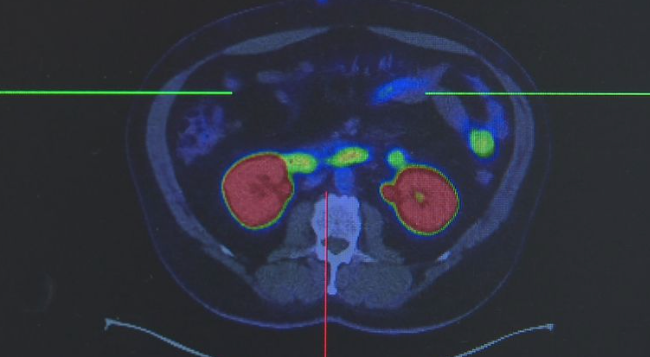

这就是目前全世界最先进的超级扫描仪:西门子Quadra PET和CT扫描机。墨尔本Theranostic创新中心引进了澳洲私人机构中的第一台!这台价值1300万澳币的扫描仪,让医生可以看到病人全身上下任何微小的异常,及时发现肿瘤。

澳洲医学教授Rod Hicks说,这台扫描仪将彻底改变癌症患者的人生。不论是心脏、肺、大脑,还是其他所有的器官,只要有异常,在这台扫描仪面前一览无余。

有了这台超级扫描仪,病人就再也不用一次次地去做B超做CT来排除病源,更不用担心会遗漏掉那些隐藏很深的癌变

癌症,将无处可藏